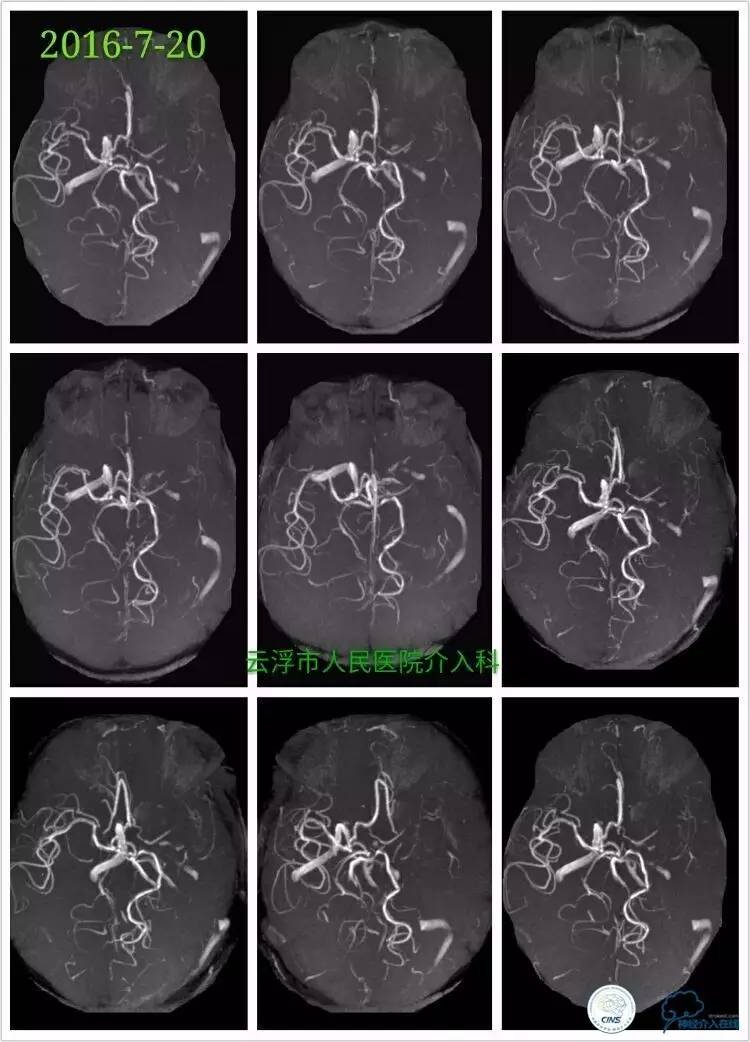

》2016-7-20

颅脑MRA检查:左侧额颞叶、基底节区、放射冠区急性脑梗塞,左侧颈内动脉颅内段重度狭窄。

行脑血管造影见:左侧颈内动脉交通段重度狭窄,左侧椎动脉开口重度狭窄,前交通、大脑前动脉、大脑后远端血管有部分代偿,左侧大脑中动脉区域侧支代偿不足。